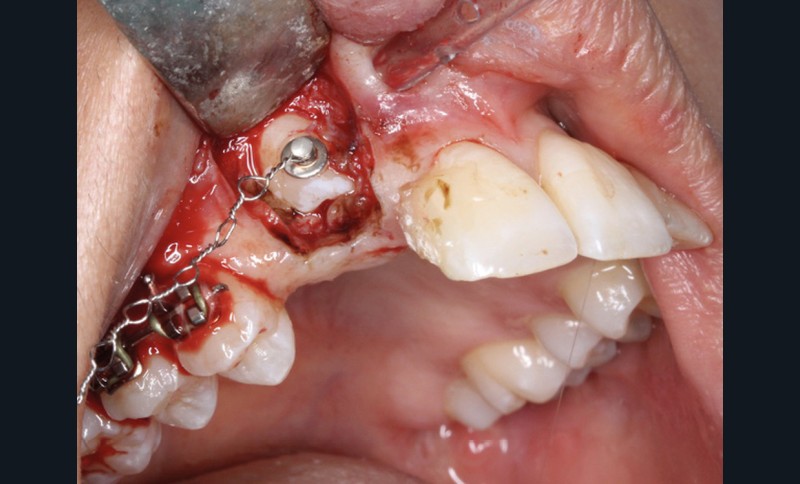

La désinclusion des canines a été réalisée dans un deuxième temps opératoire après trois semaines de cicatrisation muqueuse afin d’avoir une quantité de gencive attachée suffisante lors de la réalisation des lambeaux. Un lambeau déplacé apicalement a été réalisé pour désinclure la 13, avec une direction de traction distale sur une potence soudée sur le sectionnel activée après trois semaines de cicatrisation (fig. 3). Un lambeau muco-périosté repositionné a été réalisé pour désinclure la 23 qui a été immédiatement mise en charge par traction distale sur un bouton palatin collé sur 25. Un approfondissement vestibulaire mandibulaire antérieur a ensuite été réalisé.

La traction des canines incluses s’est faite sur des sectionnels postérieurs en TMA .017 x .025 de type Ballista (fig. 4a,b). Un décapuchonnage de la 23 a dû être réalisé pour lui permettre de transpercer la muqueuse palatine. Des cales occlusales ont été ajoutées pour assurer le passage de la canine de la situation palatine à vestibulaire. Un contrôle radiologique a permis de suivre la traction. Parallèlement, la fermeture des espaces mandibulaires s’est faite par perte d’ancrage postérieure et par redressement antérieur grâce à des chaînettes élastomériques.